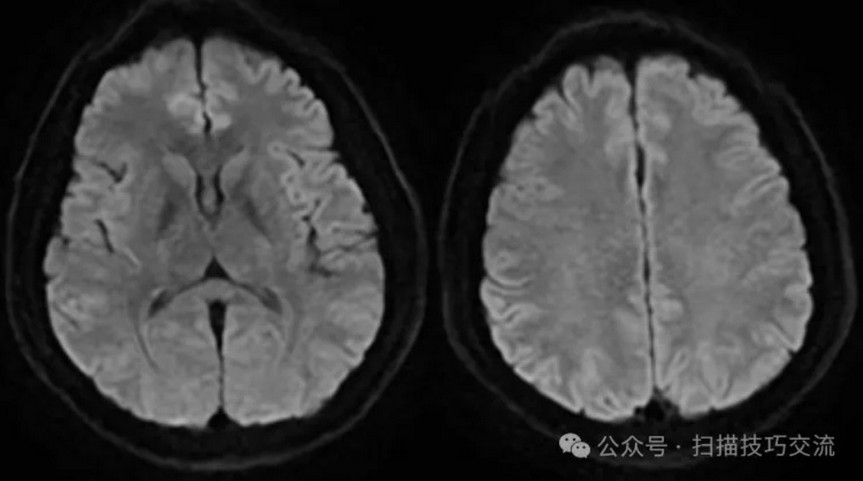

•汗腺分泌:正常,皮肤划痕正常反应。 •尿便障碍:无。性功能障碍无。 •专科情况:正常。不逐一罗列。 •辅助检查:01-05颅脑CT提示:1,上矢状窦、双侧横窦密度较高,请结合临床,必要时进一步检查;2,双侧脑室后角可疑稍高密度影,右顶叶局部脑沟密度可疑增高,建议进一步检查。 •初步诊断:静脉窦血栓

临床申请:颅脑平扫,静脉成像,磁敏感成像,颅内静脉血管黑血成像。

图像不逐一罗列,未见异常。

SWAN未见异常。

PC-MRV未见异常。

颅内静脉黑血成像,CUBE T1fs w/o +c,静脉窦未见异常。